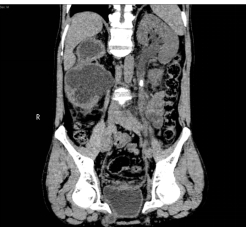

入院后,三维CT发现患者双侧输尿管结石,右肾盂输尿管连接处狭窄,右肾严重积水,左肾也因结石梗阻导致肾盂输尿管积水。肌酐1284.5μmoI/L,已经达到急性肾功能不全(尿毒症期)。王春阳教授立即为患者进行超声引导下右肾穿刺造瘘,改善患者肾功能,并制定拟行达芬奇手术机器人辅助腹腔镜下双侧输尿管切开取石术+达芬奇手术机器人辅助腹腔镜下右侧肾盂成型肾盂输尿管再吻合术,决定一次手术解决目前导致患者肾脏积水的全部问题。

王春阳教授介绍,仅利用一次手术同时处理患者全部问题,大大增加手术难度,但能减轻患者的痛苦和费用。对于结石大、梗阻明显、结石坎顿的病人,为及时解决梗阻,挽救肾功能,可选择输尿管切开取石。传统的输尿管切开取石手术疗效可靠,但患者手术创伤大,恢复慢,住院时间长。运用达芬奇手术机器人辅助腹腔镜下行输尿管切开取石术不切断肌肉,不损伤较大血管神经,手术直视下进行,术野可放大10倍,手术损伤小,出血少,恢复快。同时该病人CT中表现出右侧肾盂输尿管连接部狭窄,切开取石后行右侧肾盂成形术,去除狭窄段,对肾盂输尿管连接部重新塑形,显著解除梗阻。